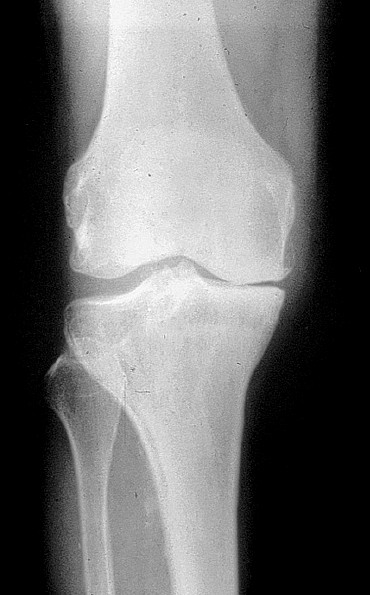

Les signes cardinaux de l’arthrose sont le pincement localisé de l’interligne articulaire dans les zones de contraintes mécaniques, l’ostéocondensation souschondrale, les géodes sous-chondrales cerclées et l’ostéophytose (figure 1.4)

Fig. 1.4. Aspect radiographique d’arthrose périphérique. Radiographie standard du genou de face en charge : gonarthrose fémorotibiale interne